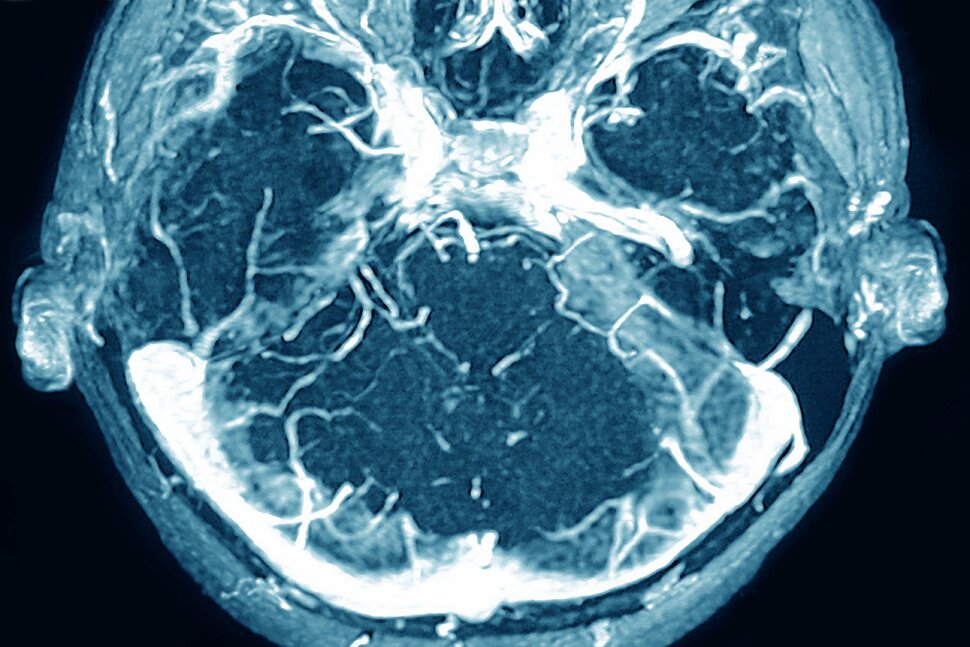

Their solution, called Viz Hemorrhage, uses AI algorithms to detect suspected brain bleeds in the hopes of reducing human error and helping institutions assess severity, monitor progression and plan treatment.

In practice, we started with intracranial hemorrhage detection – detecting acute bleeding inside of the skull – and those are cases where you almost always want to be informed immediately because they have the potential to become life threatening really quickly.

The real questions that our users were still asking is, “What does this mean for this specific patient?” Because the same bleed can have a completely different impact on a person depending on how it occurred or what their anatomy looks like. And that’s what first pushed us into the quantification, providing consistent and objective measurements like bleed volume or maximum thickness, so that our users could better assess the severity of the bleed and make decisions about treatment.

From a clinician’s perspective, this is really designed to fit within their workflow and not disrupt it. So let’s say that a patient presents to the emergency department and gets a CT scan. As soon as that scan is completed, it’s sent to the cloud and our system analyzes it automatically. If we detect a hemorrhage, you’ll receive the alert.

You can open it up, and you’ll have access to the imaging as well as those quantified outputs. Because we provide those measurements, the users can also customize which notifications they actually receive. An emergency department provider might want to receive a notification for every single bleed that walks through the door, because they’re in charge of triaging the care of that patient. But a neurosurgeon might only be interested in patients that are more likely to go for intervention.